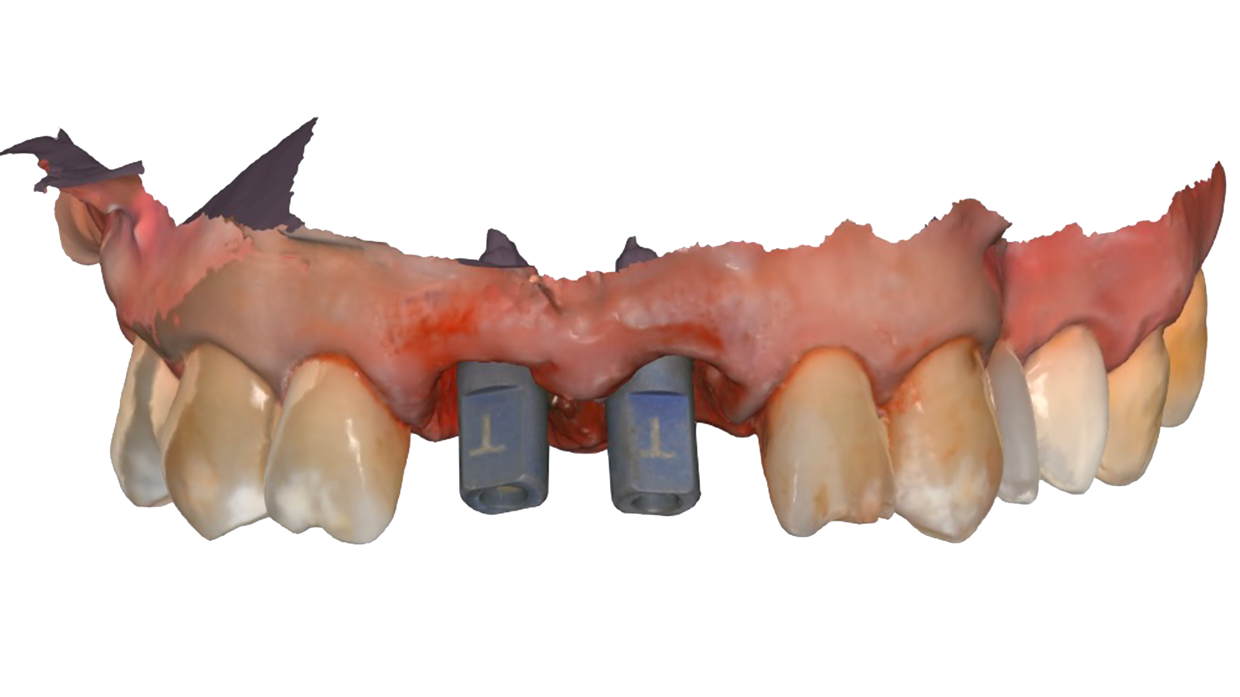

Il posizionamento degli impianti è stato pianificato prima dell'intervento su un software dedicato. In un'unica seduta, dopo l'estrazione degli elementi dentari compromessi, sono stati immediatamente inseriti gli impianti nella posizione pianificata, grazie alla realizzazione della dima chirurgica. Per ridurre il riassorbimento osseo a lungo termine e garantire quindi una maggiore resa estetica (vista la zona d'intervento), la chirurgia è stata eseguita con una particolare tecnica denominata: Socket Shield Technique.